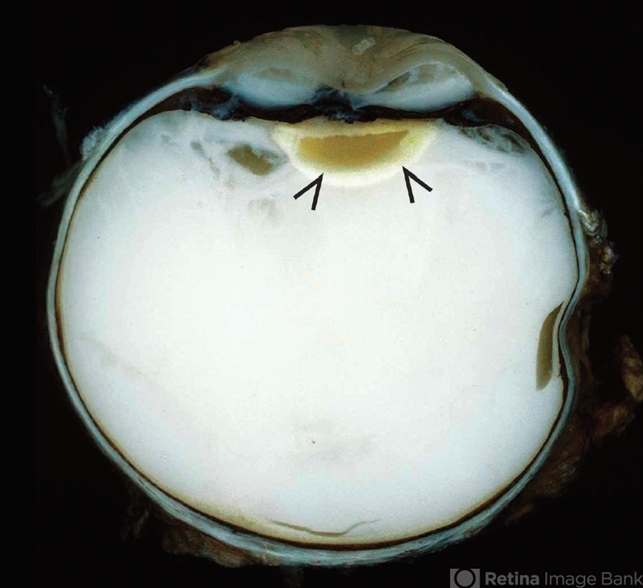

- In lens-induced uveitis, lens protein in the anterior chamber causes a zonal granulomatous response, which occurs usually 1 day to 3 weeks after capsule rupture. This may be associated with sympathetic ophthalmia. This enucleation specimen shows an indented cornea, accompanied by complete hypopyon occupying the anterior chamber with intense vitreitis. Note that the translucent vitreous has become whitish, and the lens surface is irregular with decoloration of the peripheral areas (arrows).